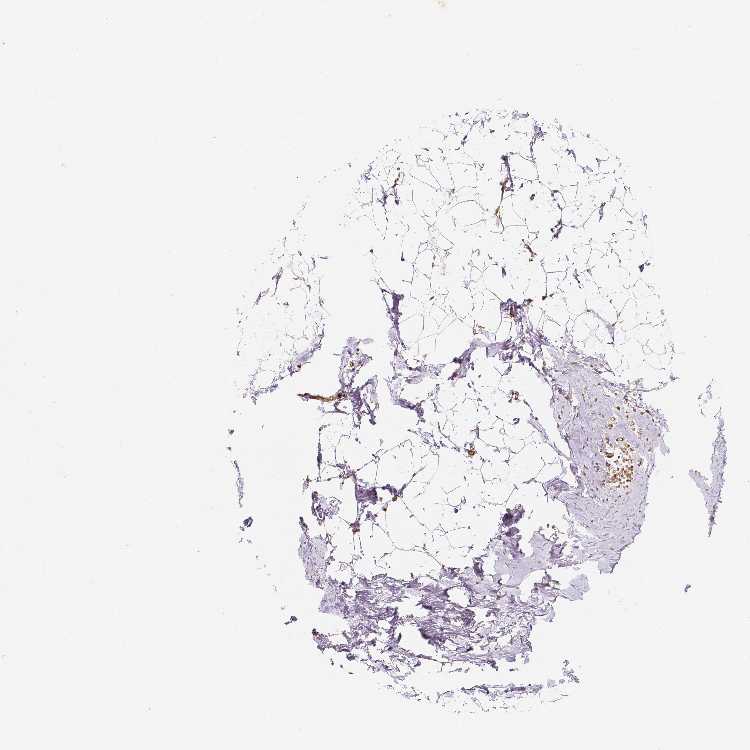

BREAST - Antibody stainingi

Antibody staining in the annotated cell types in the current human tissue is reported as not detected, low, medium, or high, based on conventional immunohistochemistry profiling in selected tissues. This score is based on the combination of the staining intensity and fraction of stained cells.

Each image is clickable and will lead to virtual microscopy that enables deeper exploration of all samples and also displays staining intensity scores, fraction scores and subcellular localization as well as patient and tissue information for each sample.

Antibody HPA023739Antibody HPA024017Antibody CAB068206Antibody CAB068207

Adipocytes Not detectedNot detectedLowNot detected

Glandular cells Not detectedNot detectedMediumMedium

Myoepithelial cells LowNot detectedLowLow